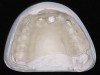

Guided implant surgery involves reverse treatment planning. The ideal contour and arch position of the restoration is planned first, followed by virtual planning of the implant into that position according to the bony anatomy and clinical scenario. SLA surgical guides are then fabricated from the treatment plan. A dental laboratory next uses the SLA guide, with mounted casts, to fabricate provisional restorations prior to implant placement. At the time of surgery, the surgical guide is used to place the implants flaplessly, removing only a tissue core in the implant site(s). Abutments are immediately placed, and provisional restorations can be inserted.15-20 (Figure 12 through Figure 17).

Although technologies are available to place immediate definitive restorations, most clinicians are placing provisional restorations, for many reasons. Whether performed flaplessly or not, after surgery the final gingival contours and anatomy cannot be predicted. The clinician and dental technician can gain invaluable information as to the gingival contours and esthetics by observing tissue responses from the provisional restoration. Whether implant placement is guided or nonguided, a small number of implant failures occur. Most surgery-related failures take place within the first 3 to 4 months after implant placement. Surgical and restorative implant failure management is best accomplished prior to insertion of the definitive restoration. According to Abrahamsson et al, changing from a healing abutment to a permanent abutment did not result in a change in the dimension and quality of the transmucosal attachment that developed. It did not differ from the mucosal barrier that formed on a permanent abutment placed after surgery.31 An acrylic resin occlusal surface or a composite restoration reduces the forces of impact and has a better shock-absorbing behaviour compared to ceramic materials32; this is an additional reason for placing immediate acrylic resin provisional restorations, rather than immediate definitive porcelain restorations.